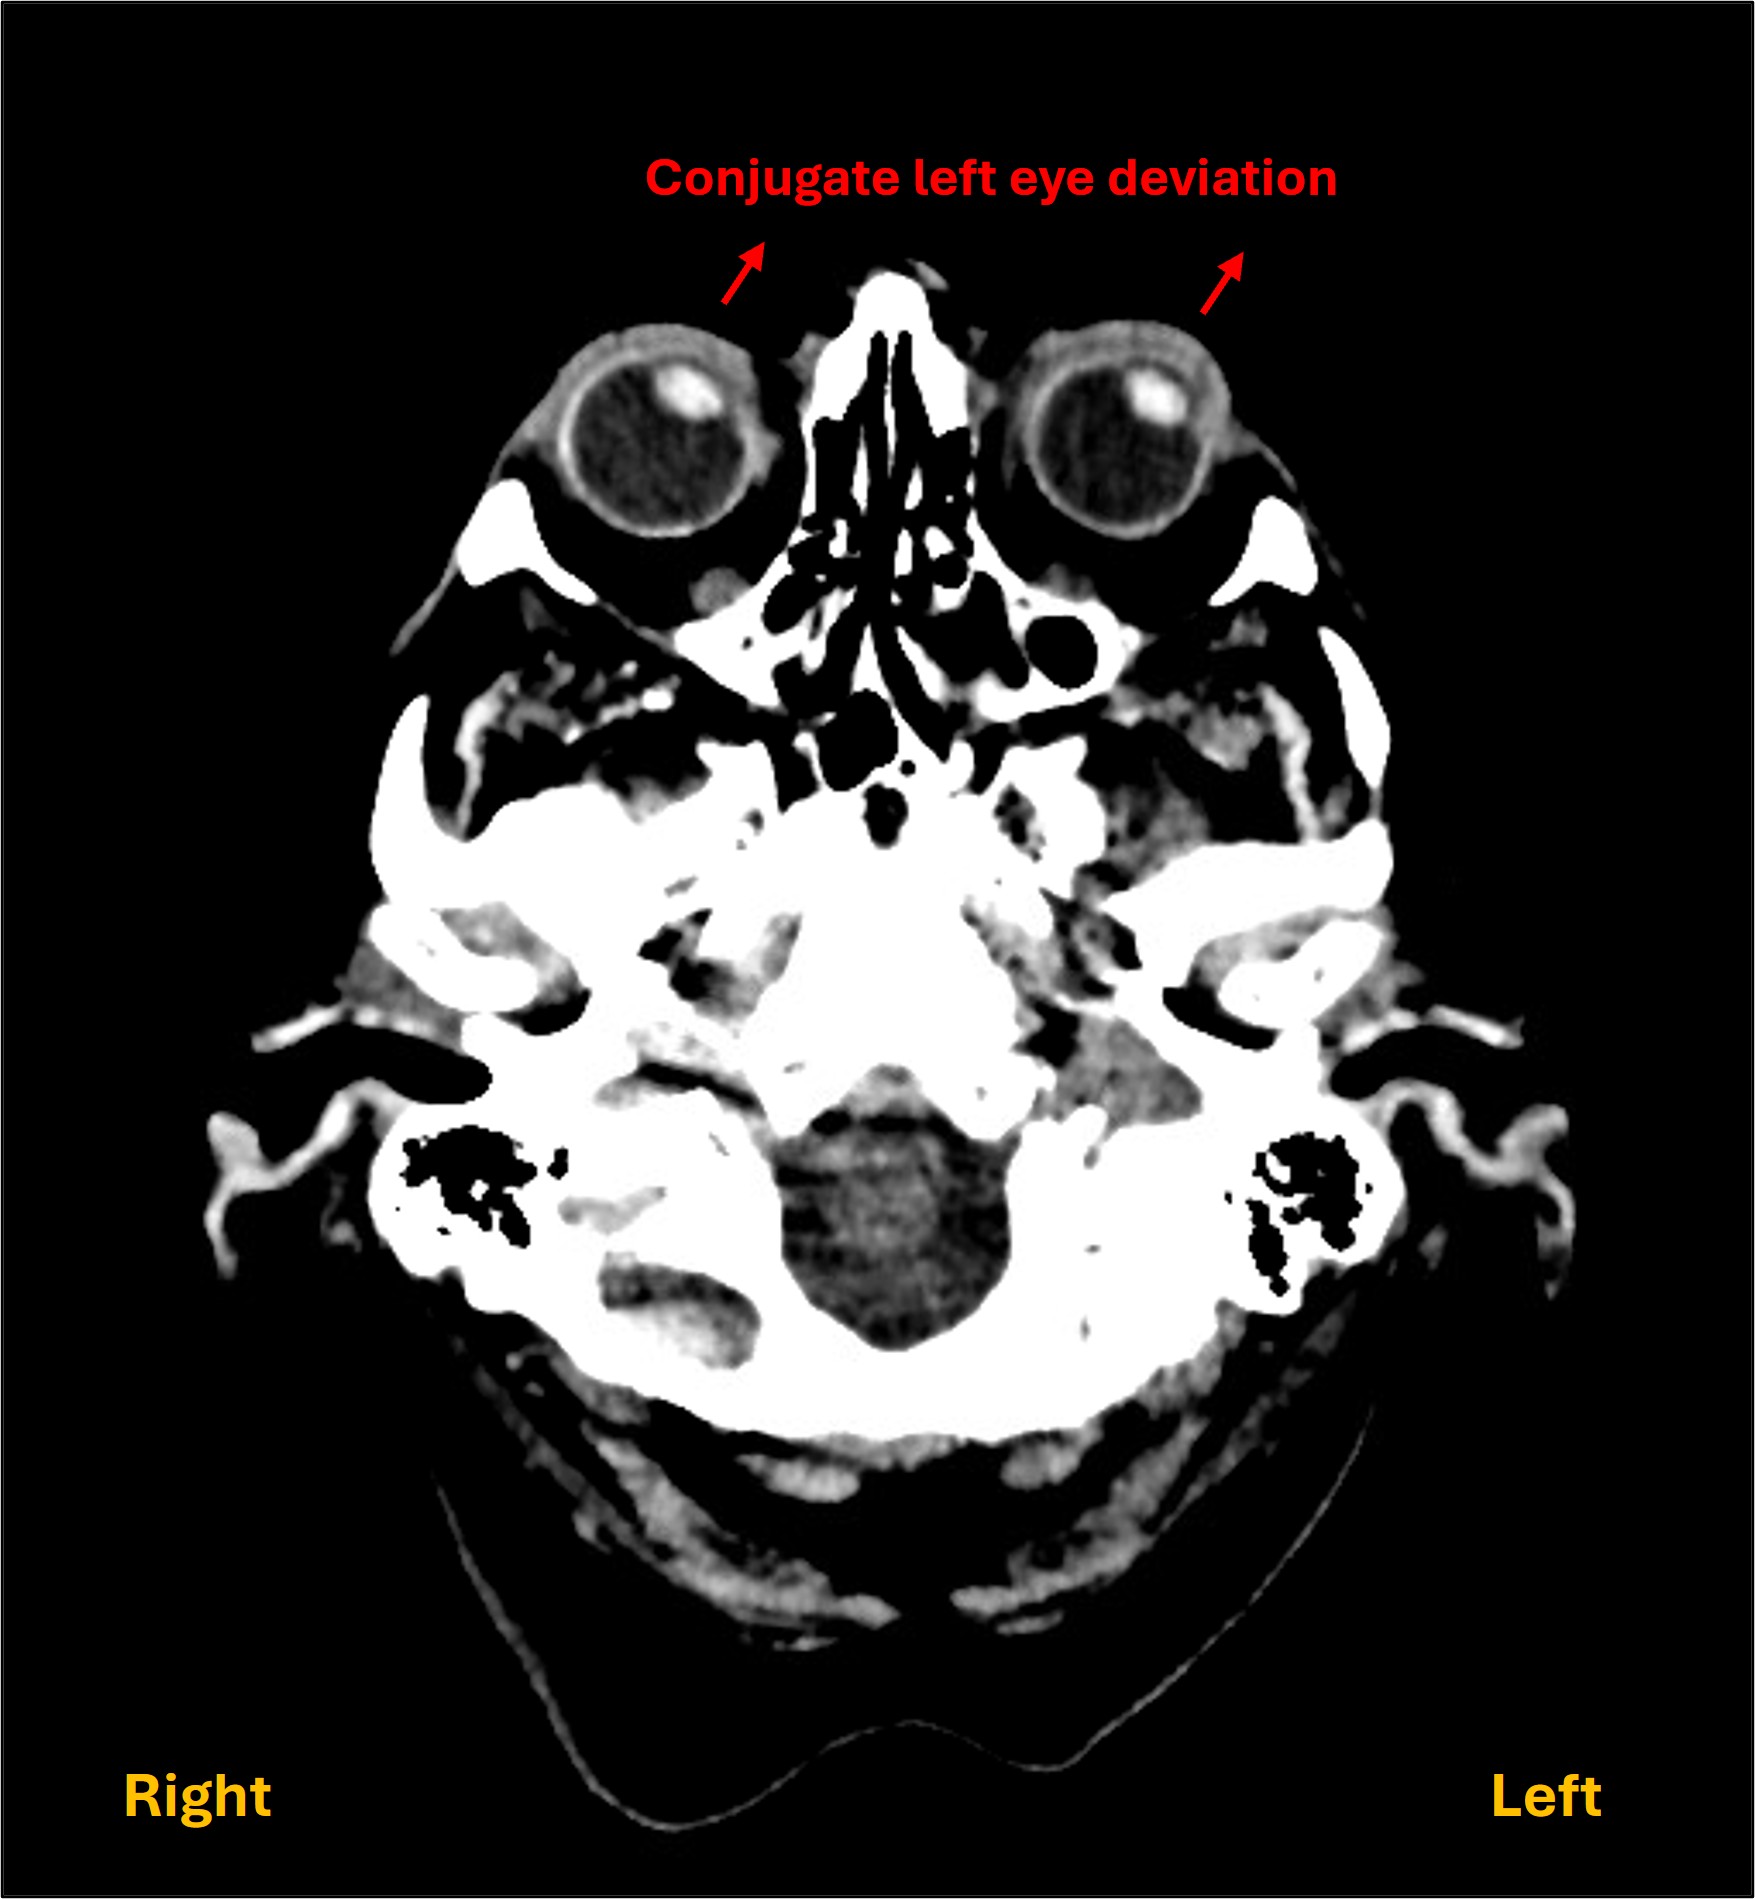

4. Leftward eye deviation

This is a helpful feature for localisation.

Conjugate horizontal eye movement requires input from the brain via the brainstem gaze centres to the muscles involved in eye movement. Problems at various sites can lead to fixed lateral gaze deviation - but we know we are dealing with a brain lesion.

While visual inattention (neglect) can lead to a tendency to 'ignore' information on one side of world, and can look similar, in that situation the patient tends to look around, just not past the midline, favouring stimuli from one side. Here the gaze is fixed to the side. This is due to involvement of the frontal eye field (FEF) in the left frontal lobe - at the junction between the precentral gyrus (motor strip) and middle frontal gyrus.

The FEF's role is to push both eyes to the opposite (right) side. Normal resting eye position ('primary position') results from tonic activity in both FEFs, with equal and opposite forces keeping the eyes central. To move the eyes rightward, the left FEFs are activated. A left FEF lesion leads to tonic push towards the lesioned left side by the intact right hemisphere’s FEF.

This eye deviation is a bedside sign, but it can also often be seen on brain imaging as an additional clue to a lesion involving the FEFs - known as Prevost's sign.

Prevost sign

Of note, the opposite happens with a left frontal lobe seizure involving the FEF - the FEF becomes over-active, pushing the eyes rightward. This is an example of an irritative lesion - in which excess activity is triggered. However, in our case, we know already there is left hemispheric damage from other features - so we are dealing with a left FEF destructive lesion.